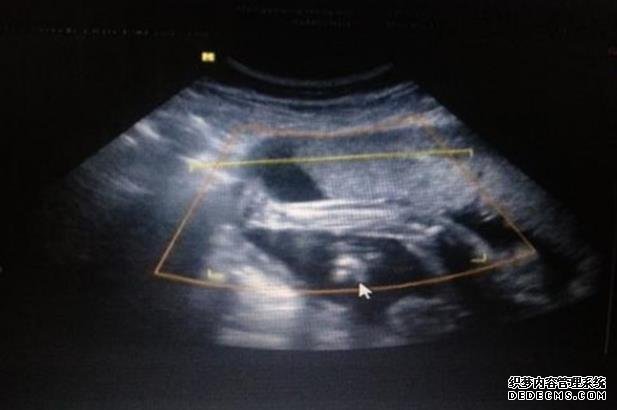

一直月经不调。结婚才重视这个问题。10月3日到医院检查,孕酮值才0,57。医生开了地屈孕酮片和中药调理贴。10月13日药吃完了,药贴也贴完了。联系大夫让我正常来月经再去检查,没想到第2天就正常了,17号和老公请假去检查,喝1500ml水查腔内彩超差点要了我的命,喝到吐,结果进去查两次都说我尿量不够出来继续喝水,溜达。检查结果孕酮升高到标准值,医生给开了顺珈侬,促进排卵和怀孕,26号再去复查,希望指标一切正常,迎一个猪宝宝